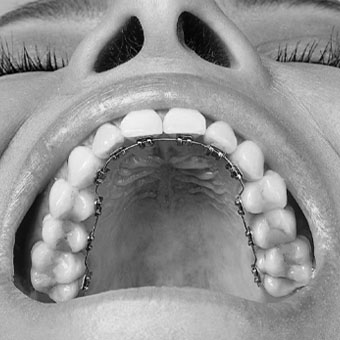

Brackets Linguales

- Es un tratamiento de ortodoncia fija.

- Posee un costo más elevado este tratamiento.

- Estéticamente no se ven los brackets desde una vista de frente.

- Esta especialidad, requiere que el paciente sea riguroso con el uso de su cepillo dental para que no queden restos.

- El paciente se demora entre 1 a 3 semanas en acostumbrarse a este tipo de ortodoncia.

- Reduce el riesgo de sufrir cortes en los labios.